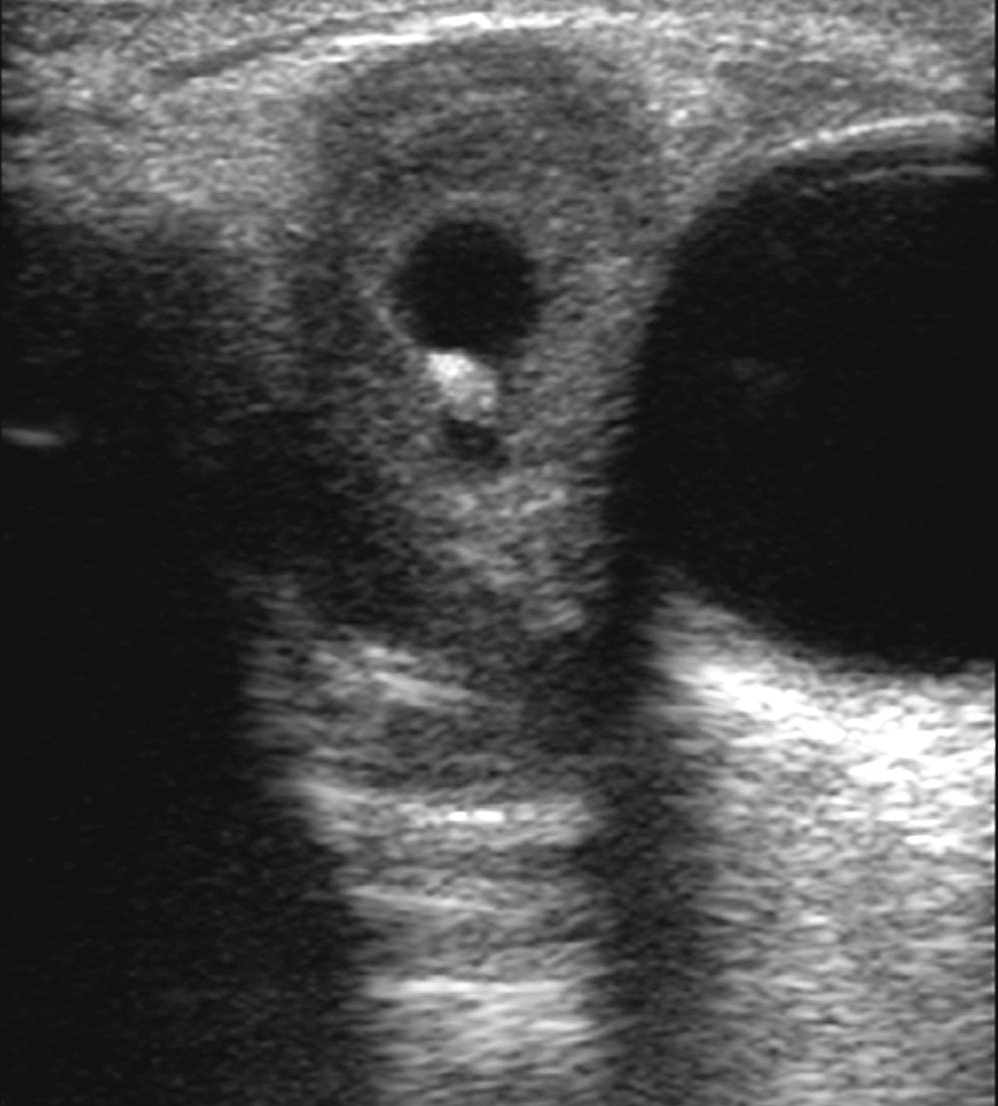

The ocular involvement of the cysticercosis is a rare entity involving eyelids, extraocular muscles, orbit, conjunctiva, anterior chamber, uvea, retina, vitreous and optic nerve. All the extraocular muscles are involved in myocysticercosis. Ultrasonography and Computed tomography are the imaging modalities for evaluation of ocular cysticercosis. The patients can be treated with systemic steroids and albendazole; however surgical excision is the treatment of choice. We report a rare case of extraocular myocysticercosis in nine years old boy diagnosed on ultrasonography and computed tomography.